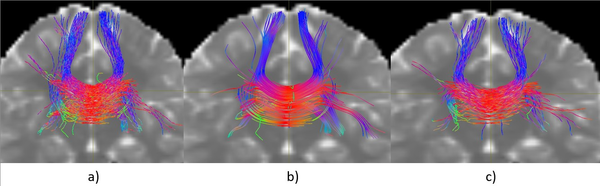

La Figura 1 muestra una comparación visual de tres tractografías generadas a partir de una misma semilla localizada en el cuerpo calloso, utilizando diferentes algoritmos. Todas las tractografías fueron generadas con la misma cantidad de trayectorias, lo que permite una observación cualitativa más equitativa entre métodos.

A partir de esta visualización inicial pueden identificarse algunas diferencias notables entre las tres reconstrucciones. El algoritmo iFOD2 (Figura 1a) presenta una mayor dispersión de trayectorias hacia regiones laterales, algo que puede relacionarse con su naturaleza probabilística, propensa a explorar recorridos menos restringidos. SD-Stream (Figura 1b) exhibe una estructura más centralizada y simétrica en la región del cuerpo calloso; las trayectorias aparecen más alineadas, aunque ello podría limitar la cobertura en zonas periféricas. El algoritmo propuesto (Figura 1c) parece mantener un equilibrio entre coherencia espacial y extensión: las trayectorias se distribuyen dentro de un rango anatómicamente plausible y sin una dispersión excesiva. Estos resultados corresponden únicamente a una inspección visual preliminar.

Comparación visual de tractografías generadas desde una semilla en el cuerpo calloso: a) iFOD2, b) SD-Stream, c) Algoritmo propuesto.

Figura 1: Comparación visual de tractografías generadas desde una semilla en el cuerpo calloso: a) iFOD2, b) SD-Stream, c) Algoritmo propuesto.